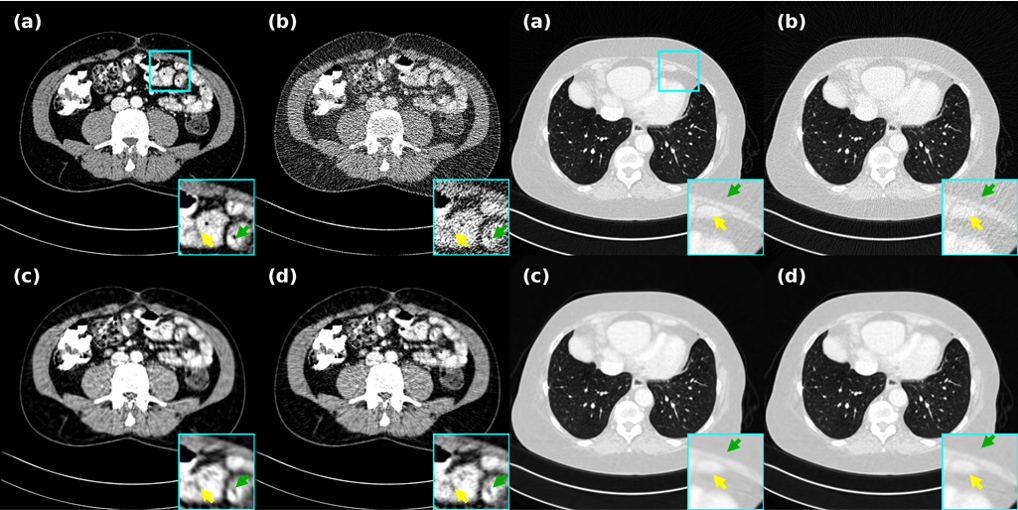

4.5.2 Experimental results on tunable generalization

Self-supervised based methods are commonly associated with a significant decrease in generalization effect when the pre-trained model of a single dose is applied to different doses, fortunately this study in demonstrated the feasibility and superiority of generalization at different doses. On the basis of this, we propose an adjustable generalization strategy for upper and lower doses as shown in Fig. 4 to maximize the model effect. As shown in Fig. 8 and Table 2, for the generalization of abdominal data for the lower dose dose, this study presents a breakthrough lead in both numerical and image effects. For AdaReNet, although it performs slightly better than us for the lung data, it shows a discontinuous drop for the abdominal data, and our model even eliminates the shot noise due to the bones, which other methods do not have the ability to do. In addition, the difference between the upper and lower dose strategies exhibited in Fig. 8 is a good indication of the correctness of the generalization strategy for adjustability. Meanwhile, inspired by NEED[47], we also apply this strategy to the LIDC-IDRI pre-trained model to generalize Mayo’s data to validate the reconstruction ability on unseen datasets.

4.5.3 Representation of real clinical data